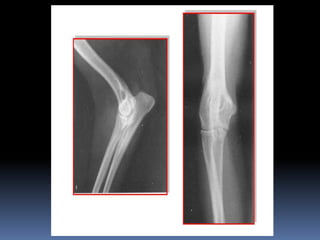

Juana, la iguana

Sam, el costurero